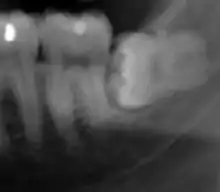

Panoramic radiograph of impacted lower wisdom teeth (green arrows) in a 26-year-old with dental caries (red arrows) on the adjacent teeth

The diagnosis of impaction can be made clinically if enough of the wisdom tooth is visible to determine its angulation, depth, and if the patient is old enough that further eruption or uprighting is unlikely. Wisdom teeth continue to move to the age of 25 years old due to eruption, and then continue some later movement owing to periodontal disease.[18]

If the tooth cannot be assessed with clinical exam alone, the diagnosis is made using either a panoramic radiograph or cone-beam CT. Where unerupted wisdom teeth still have eruption potential several predictors are used to determine the chance of the teeth becoming impacted. The ratio of space between the tooth crown length and the amount of space available, the angle of the teeth compared to the other teeth are the two most commonly used predictors, with the space ratio being the most accurate. Despite the capacity for movement into early adulthood, the likelihood that the tooth will become impacted can be predicted when the ratio of space available to the length of the crown of the tooth is under 1.[5]:141